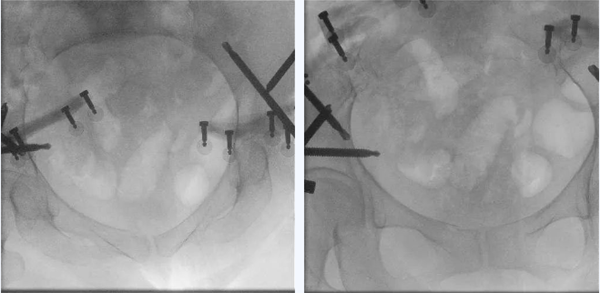

术中,在智能化骨折复位机器人的辅助下,由创伤骨科赵春鹏主任医师主刀的骨盆骨折全流程微创手术不到2个小时顺利结束,取得了与术前规划相一致的非常理想的复位和固定效果。

手术期间,Pierre Guy教授与吴新宝副院长,赵春鹏主任医师、李宇能副主任医师共同探讨手术方式,以及螺钉植入物的验证方法。赵春鹏主任医师边做手术操作,边介绍此款机器人的特点和操作流程。国内外骨科医生在手术室里展开了一场顶尖技术的学术研讨。

看到机器人成功将骨盆复位,Pierre教授十分兴奋,详细询问各种操作方法及工作原理。“It's amazing!”他由衷地赞叹这款来源于临床需求,历经十年的医工协同创新研发的智能化骨折复位机器人,并高度肯定了中国原创的智能化骨折复位机器人将带来的临床变革。

图丨复位完成透视验证